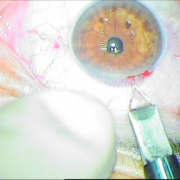

καταρράκτης με τραυματική

ρήξη οπ.περιφάκιου από

έγγχυση ANTIVGEF παράγοντα

του οπ. περιφάκιου